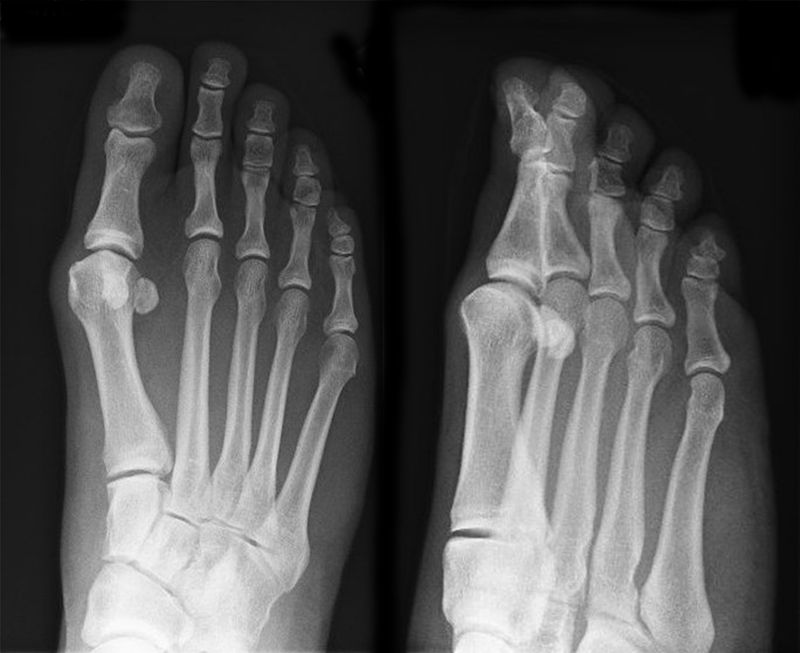

• Die Operationsplanung erfolgt anhand der Röntgenaufnahmen des Vorfußes unter Belastung in 2 Ebenen. Für die Verfahrenswahl sind wichtig der Intermetatarsalwinkel und die Breite des Os metatarsale, der Hallux valgus Winkel, der distalen Gelenkflächenwinkels (Distal Metatarsal Articular Angulation - DMAA), des Metatarsaleindex und Sesambeinposition (Abb. 1).

• Mittelgradige bis schwere Hallux valgus Fehlstellung (Intermeterversalvinkel ab ca. 15°)

• Bei hohem Hallux valgus Winkel oder pathologischem Gelenkflächenwinkel besteht die Indikation zu einer zusätzlichen Isham Osteotomie 2, die im Wesentlichen der offenen Reverden Green Osteotomie entsprecht.

• Röntgenkontrollen (Vorfuß d.p. und seitlich) postoperativ ohne Belastung. Weitere Kontrollen erfolgen 6 Wochen, sowie 3, 6 und 12 Monate jeweils unter Belastung.